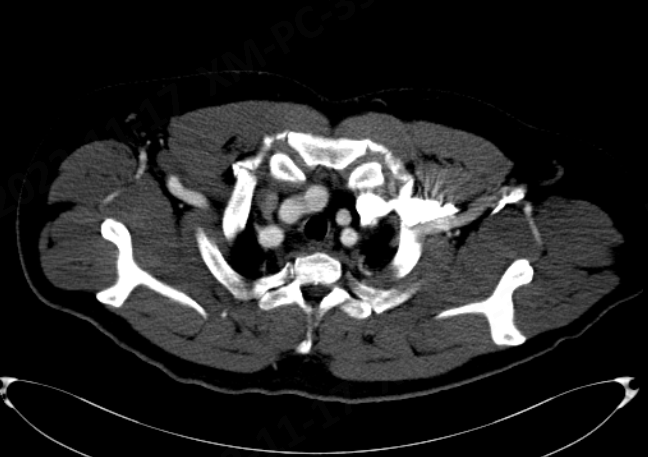

CT辅助检查

1、Stanford B型胸主动脉夹层;

2、夹层近端逆撕靠近LCCA,远端累及至脏器区动脉,降主多发小破口。

动脉长鞘怎么置入【弓部重建直通车】真腔难觅,另辟蹊径|潍坊市人民医院血管外科运用Castor®支架结合长鞘建立导丝通路治疗主动脉夹层两例_https://www.jmylbn.com_新闻资讯_第12张

CTA三维重建

动脉长鞘怎么置入【弓部重建直通车】真腔难觅,另辟蹊径|潍坊市人民医院血管外科运用Castor®支架结合长鞘建立导丝通路治疗主动脉夹层两例_https://www.jmylbn.com_新闻资讯_第13张

CTA平扫